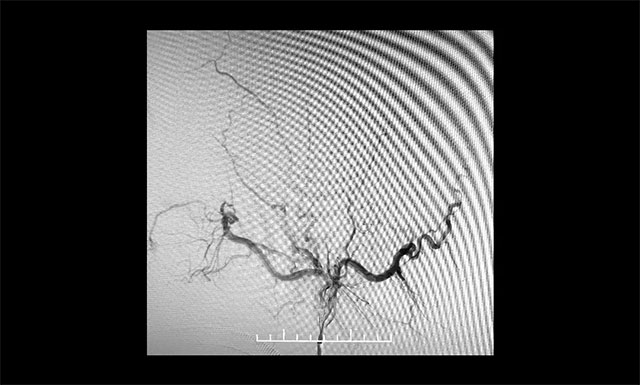

術(shù)畢鑄型

▲術(shù)畢鑄型